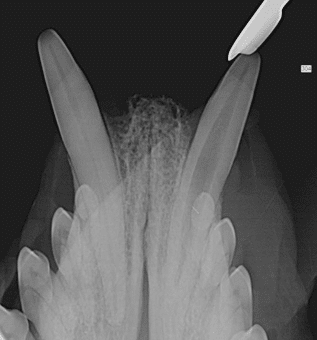

Naast dat het wortelkanaal zich ontwikkeld met ouder worden, ontwikkeld ook de wortelpunt zich. Bij jonge dieren is de wortelpunt nog niet volledig gesloten en nog deels ‘versmolten’ met het kaakbot. Dit zorgt ervoor dat extracties van zo’n element een stuk lastiger is, en soms haast onmogelijk, dan dat het extraheren van een volwassen element is.

Op onderstaande afbeeldingen is goed het verschil te zien tussen een jonge hoektand en een volwassen uitontwikkelde hoektand. Op de linker afbeelding bij de rode pijl is de nog niet gesloten wortelpunt te zien. Op de rechter afbeelding is een volwassen doorontwikkelde hoektand te zien.